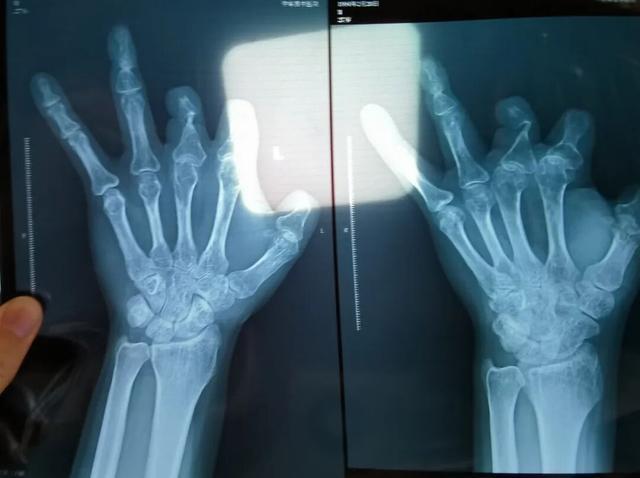

患者王海森左手拇指关节以上部位被电锯切断,收费单显示术中使用了微血管吻合装置,但X光片中未显示该器械。新京报记者 程亚龙 摄

单价1.68万元,声称在术中植入体内、用于缝合血管的两个环形吻合装置,竟然在王海森的X光片上消失了。

装置上带有不锈钢针,不可能被人体吸收,唯一的可能就是“手术时其实没有使用”。尽管之前也有其他人向王海森透露过这一点,但直到看到片子前,他一直都不相信。

该产品的代理商曾向新京报记者证实,微血管吻合装置为植入型医疗器材,患者拍摄X光片时会有显示。新京报记者获取了一位曾在郑大一附院接受手术、使用了该产品的患者的X光片,其手术部位可见一绿豆大小的光圈。

三年后,他在别人的建议下,在老家医院拍了X光片。当月——2021年12月底,王海森报了案。

2021年12月,患者彭先生拍摄的左手X光片,未见收费单据中列出的微血管吻合装置。新京报记者 程亚龙 摄